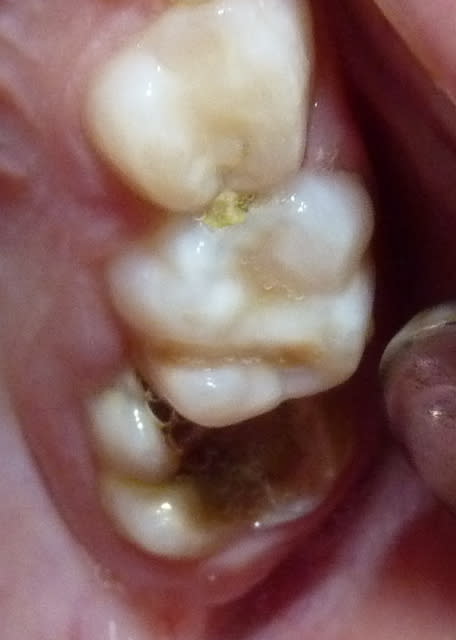

Qui ferait quoi dans le cas ci-dessous : 11 ans, patient en classe I, normodivergent, hygiène médiocre, très coopérant au fauteuil. 36 présente une carie similaire en lingual. Ces deux dents sont vitales.

De plus, les 5 peuvent aussi rester bloquées par la bascule des 4 et 7... vu la pano... et les germes des 8 ont l'air pas mal...